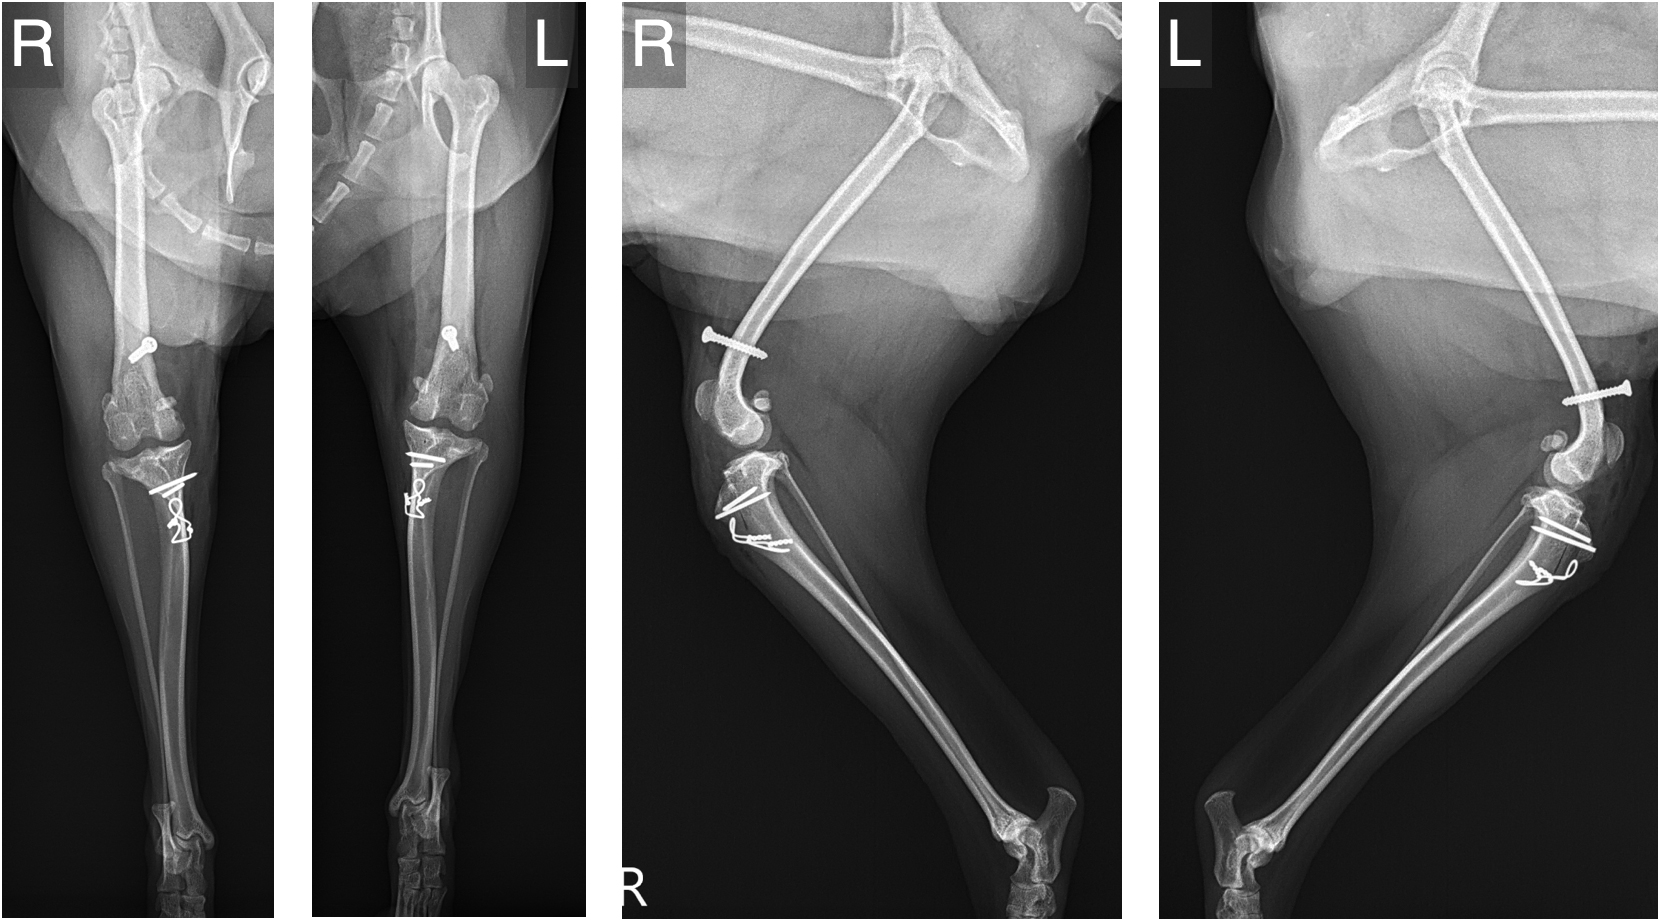

重度の膝蓋骨脱臼グレード4では、骨の変形や靭帯・関節包の異常など、複数の要因が重なって後肢の歩行機能に重大な問題を引き起こしています。

当院では、こうした症例に対して以下のような手術手技を症例ごとに適切に組み合わせ、「歩けるようになること」、「痛みなく生活できること」を目指しています。

骨の変形が疑われる場合には、以下のような段階を踏んで安全かつ精度の高い手術を行います。

※骨変形が高度な場合、滑車溝形成術と矯正骨切り術を分割して実施することで、安全性と整復精度を確保します。